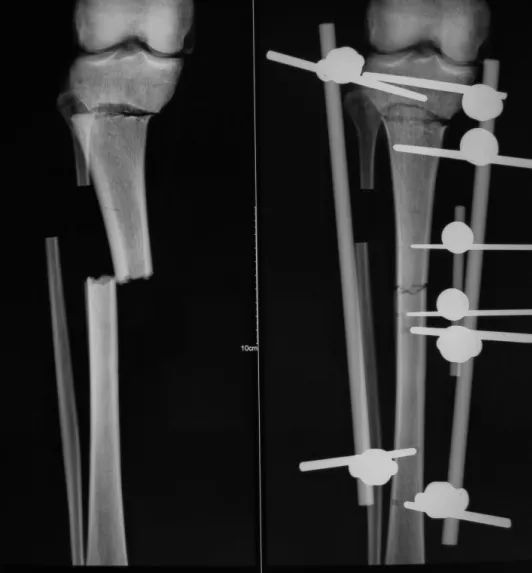

下面1例是我的学生所发。病史清楚,跗骨骨折后伤口开放,每次换药用双氧水冲洗伤口,造成骨坏死

跗骨感染

该例患者需要汲取的经验和教训:不要使用双氧水冲洗伤口死骨密度高是因为不参与代谢周围骨疏松治疗清理死骨后用骨水泥诱发诱导模反复几次做半开放植骨手术后走路刺激骨愈合,改善骨质愈合。